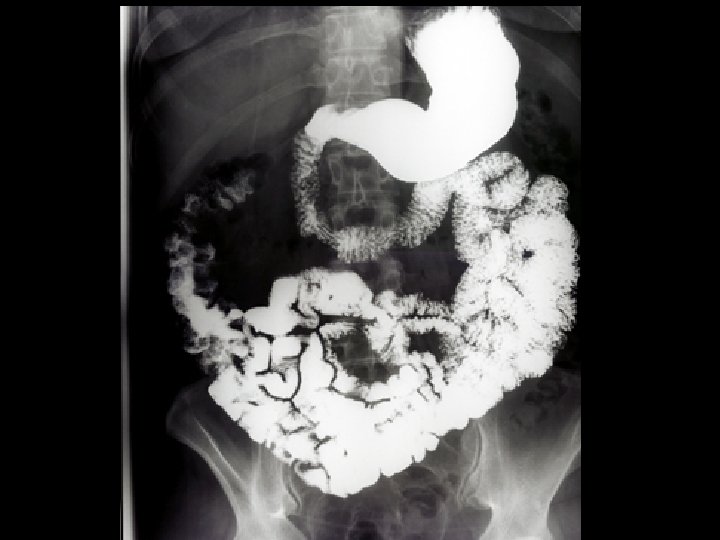

FLUOROSCOPY IMAGES IN MOTION